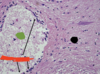

18

Pia mater

19

Red –> arachnoid space

Blue –> subarachnoid space

20

Arachnoid mater

21

Black –> arachnoid mater

AT –> arachnoid trabeculae